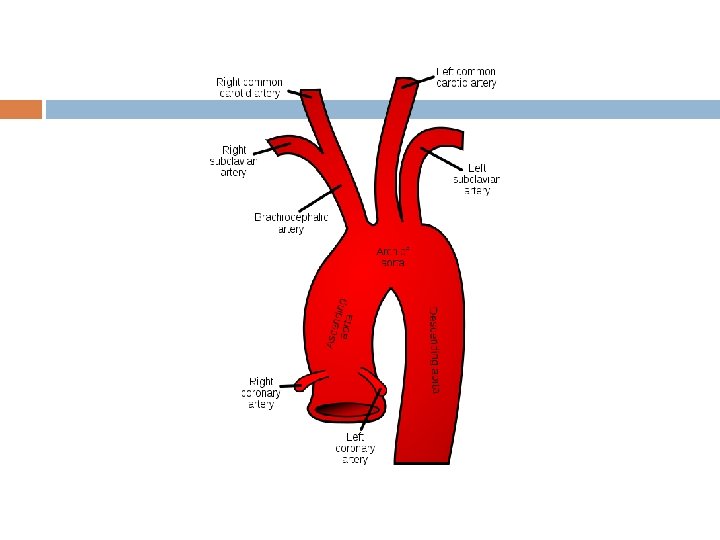

Aorta � Ascending begins � rt Aorta @ aortic semilunar valve & lt coronary arteries supply � Aortic rt & lt sides of heart Arch 3 important branches: brachiocephalic trunk, lt common carotid, lt subclavian � Descending travels Aorta posterior to heart portion in thorax called thoracic aorta Portion in abdominal cavity called abdominal aorta

Common Carotids branch into: External Carotid arteries � supply blood to neck, esophagus, pharynx, lower jaw, face Internal Carotid arteries � supply blood to the brain (with the rt & lt vertebral arteries: branches of subclavian arteries)

Arteries of Upper Extremities Axillary artery: � branch of subclavian artery � becomes Brachial artery in the arm branches into Radial (pulse)& Ulnar arteries in lower arm